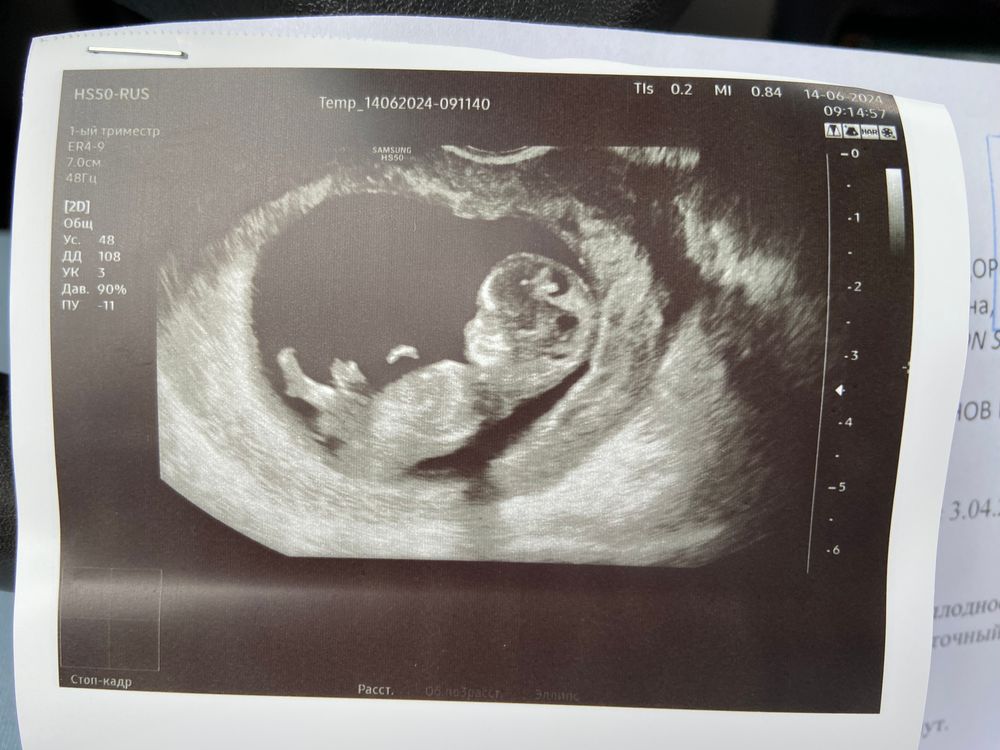

оставлю это тут 10+2

Моя рыбка, уже 40 мм, по узи ставят 10 нед 5 дней, опережаем на три дня) показали длинные ножки, ручки , мозг формируется, но уже есть два полушария, глазницы, нос и ротик))) там уже маленький человечек, не могу глазам поверить что 40 мм это 4 см и уже такой внешне сформированный